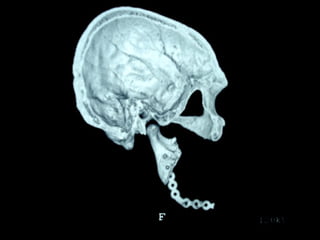

Trismus importante debido a que

El tumor ya rompió el hueso com-

Pacto de la cara interna de la

Mandíbula y empezó a tomar el

Músculo pterigoideo interno y

milohioideo.

Sierra de GigliSierra de Gigli

Luxación de hemimandíbula

Pieza quirúrgica

Plantilla flexible para dar forma previa al implante

Se respetó el cóndilo para anclar la prótesisSe respetó el cóndilo para anclar la prótesis

Límite tumoralLímite tumoral

Area de lisis ósea a nivel de la línea

Miliodes que contracturó los músculos

Milohioideo y pterigoideo interno

Dificultando la deglución y determinando

Trismus importante.

Pieza en proceso de examen por histopatología

Dr. Ismael Espejo Plascencia Patólogo

48 horas de post-operatorio

Maxilectomía parcial